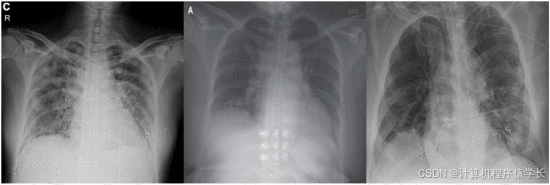

本文提出了一种轻量级深度学习模型,以准确筛查COVID-19肺炎的可能性。该模型基于14层卷积神经网络(CNN)和改进的空间金字塔池化模块(SPP),通过使用SPP的并行池层替换原始网络的最后几层来嵌入多尺度特征向量,实现的模型对各种输入尺度图像具有鲁棒性,能够适应各种大小的X射线图像,并捕获其中的图像特征。所构建的模型结构具有对多尺度输入图像进行特征提取的能力,使其能够识别各种严重程度的COVID-19疾病。根据实验结果,所提出的SPP-COVID-Net得到了0.946的精度,最后本文将该模型应用到系统页面,做了一个可用于分类不同类型肺炎的轻量级检测网站,医生可以立即运行,以便自动执行筛查过程。